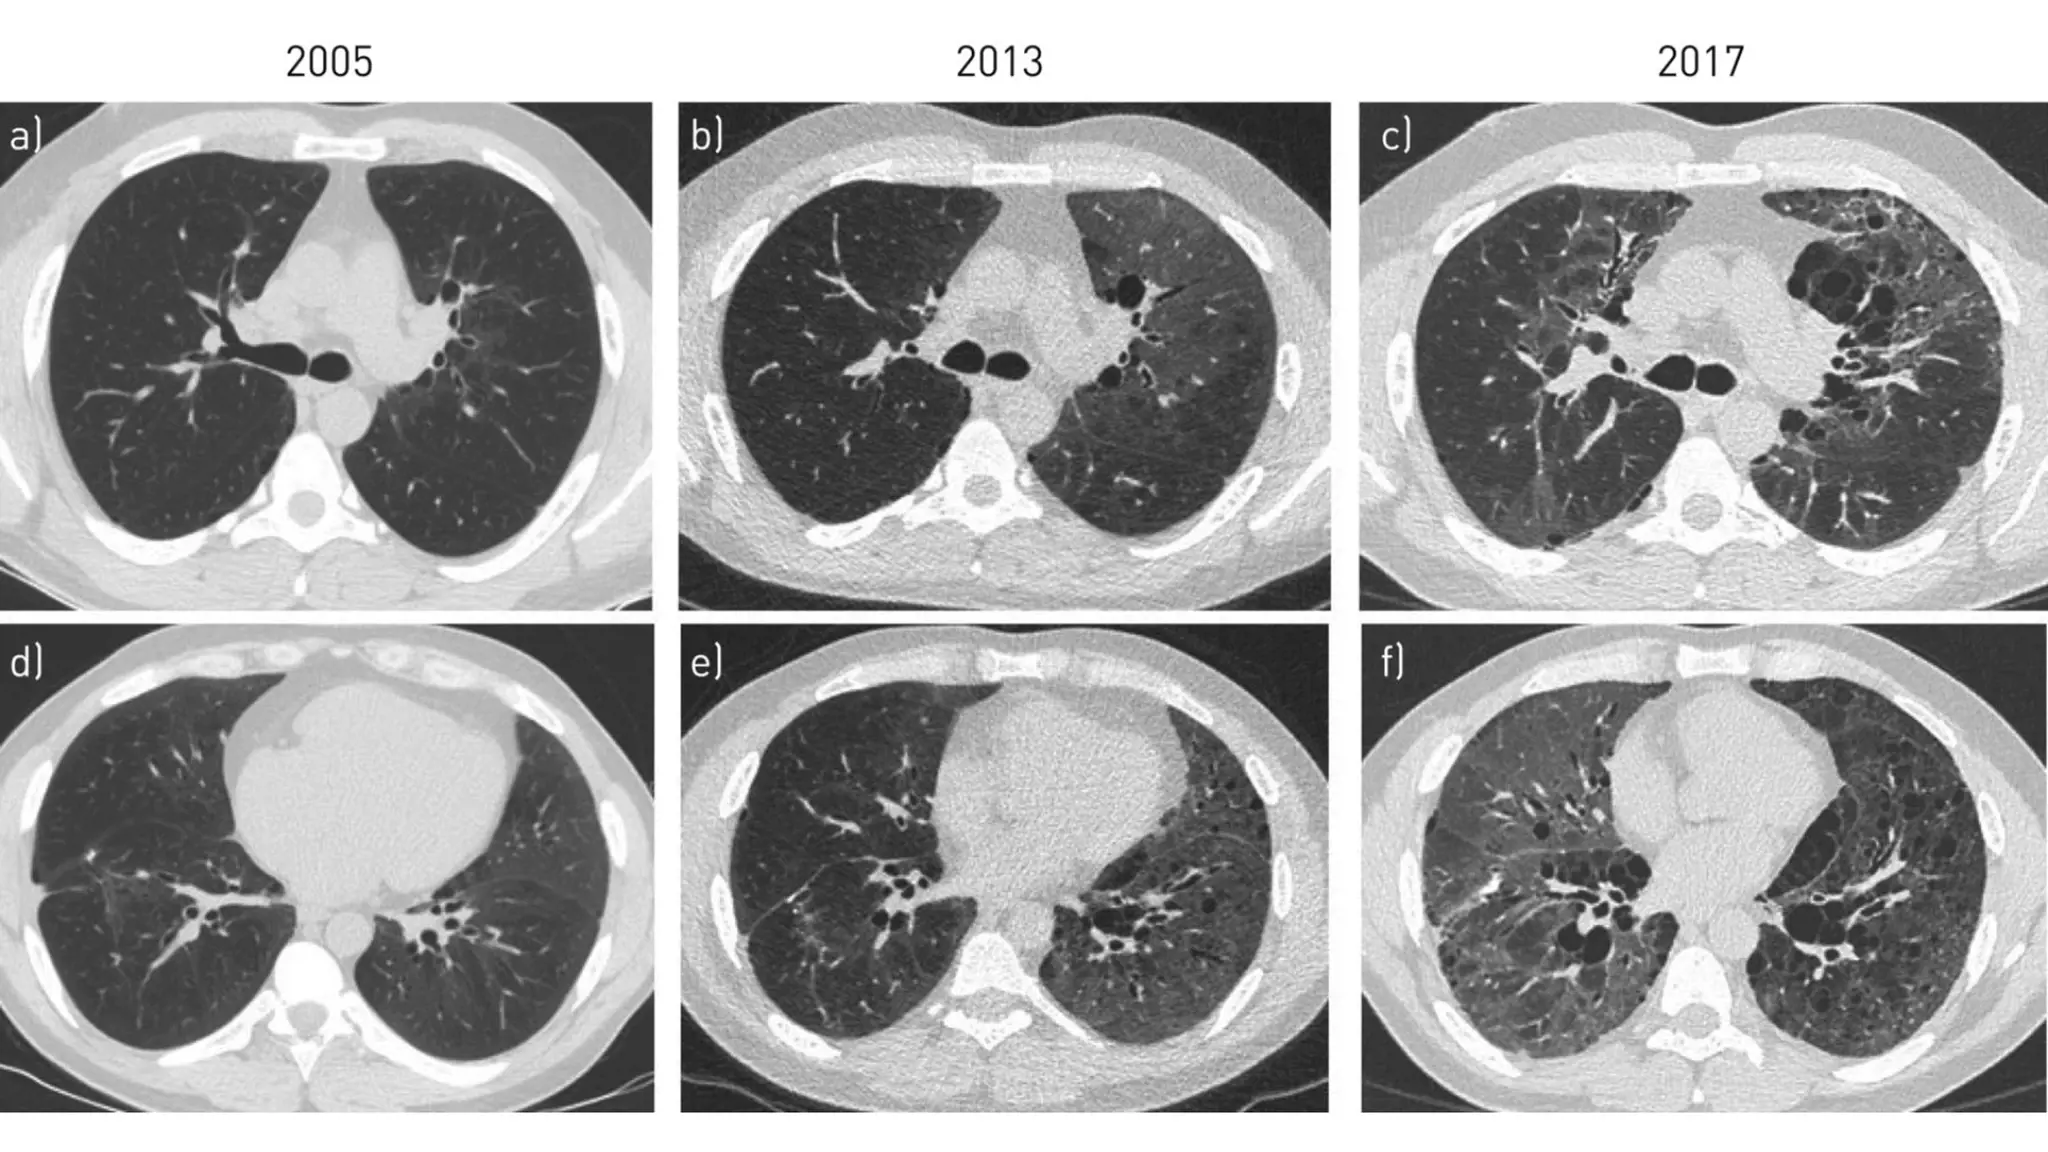

- X-quang hộp sọ: Có thể nhìn thấy sự mòn hoặc vết nứt trên xương sọ.

- CT-scan hộp sọ: Tạo hình ảnh 3 chiều, cho thấy xương sọ của bạn có bị bào mỏng đi hay không hoặc liệu có khối u đang tồn tại hay không.

- MRI (chụp cộng hưởng từ): Cho thấy hình ảnh chi tiết về xương sọ cũng như các cấu trúc xung quanh hộp sọ. Xét nghiệm này có thể gợi ý nguyên nhân gây ra tình trạng tiêu xương sọ.